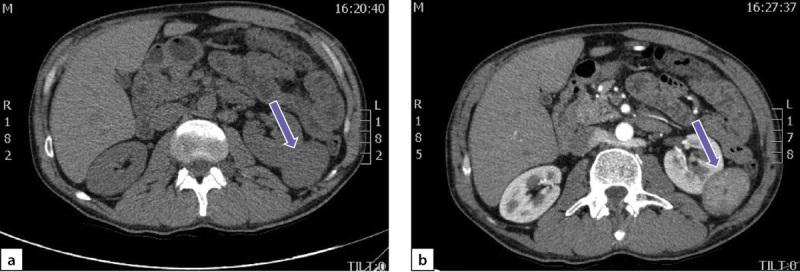

We presented the clinical case of neurofibromatosis type 1 (NF-1) associated with pheochromocytoma (PHEO) in a man under 40 years old without family history. The diagnosis of NF-1 was established based on 4 signs of the disease (multiple café au lait macules, scoliotic changes in posture, the presence of multiple neurofibromas, Lisch nodules). The diagnosis of PHEO was determined by a significant increase of free metanephrin/normethanephrin levels in daily urine, a malignant CT phenotype of the right adrenal tumor, and confirmed by pathomorphological study. Genetic tests revealed a new mutation in one of the alleles of NF1 gene, a deletion of a 566 bp gene fragment, including exon 19 with a size of 73 bp. This mutation leads to splicing of exons 18 and 20, frameshift, and termination of protein synthesis. A study of the level of transcription of the genes associated with PHEO (RET, TMEM127, MAX, FGFR, MET, MERTK, BRAF, NGFR, Pi3, AKT, MTOR, KRAS, MAPK) was conducted, a statistically significant decrease in the level of transcription of the KRAS and BRAF genes and increase in the level of transcription of the TMEM127 gene in comparison with control samples have been detected. This case demonstrates the need for timely recognition of NF-1 for further appropriate patient's follow up and show the effectiveness of a multidisciplinary approach to the diagnosis and treatment of NF-1-associated catecholamine-secreting tumors.

我们报告了一例1型神经纤维瘤病(NF-1)合并嗜铬细胞瘤(PHEO)的临床病例,患者为一名40岁以下无家族病史的男性。NF-1的诊断基于该疾病的4项体征(多个咖啡牛奶斑、脊柱侧弯姿势改变、多个神经纤维瘤、Lisch结节)。PHEO的诊断通过每日尿液中游离甲氧基肾上腺素/去甲氧基肾上腺素水平显著升高、右肾上腺肿瘤的恶性CT表型确定,并经病理形态学研究证实。基因检测发现NF1基因的一个等位基因发生新突变,一个566 bp基因片段缺失,包括73 bp的外显子19。该突变导致外显子18和20拼接、移码并终止蛋白质合成。对与PHEO相关的基因(RET、TMEM127、MAX、FGFR、MET、MERTK、BRAF、NGFR、Pi3、AKT、MTOR、KRAS、MAPK)的转录水平进行了研究,与对照样本相比,检测到KRAS和BRAF基因的转录水平有统计学意义的降低,TMEM127基因的转录水平升高。该病例表明需要及时识别NF-1以便对患者进行进一步的适当随访,并显示了多学科方法诊断和治疗NF-1相关儿茶酚胺分泌肿瘤的有效性。